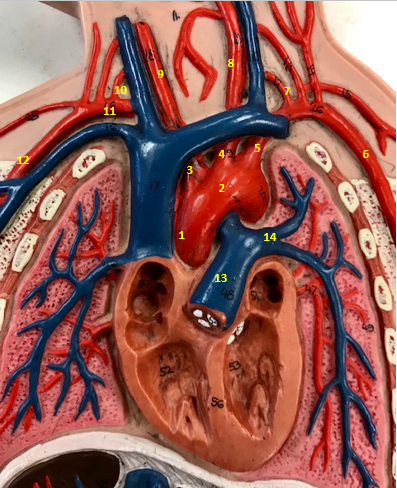

Aorta

Name #2

Brings blood out of left ventricle

Function of aorta

Brachiocephalic artery

Name #3

Supplies oxygenated blood to right arm shoulder neck and head

Function of brachiocephalic artery

Left common carotid artery

Name #4

Supplies oxygenated blood to left neck and head

Function of left common carotid artery

Left subclavian artery

Name #5

Supplies oxygenated blood to left arm shoulder

Function of left subclavian artery

Left axillery artery

Name #6

supplies blood to left armpit and upper limb

Function left axillary artery (6)

Left vertebral artery

Name #7

Supplies blood to brain and spinal cord

Function of left vertebral artery (7)

Left common carotid artery

Name #8

Supplies blood to left neck and head

Function of left common carotid artery (8)

Right common carotid artery

Name #9

Supplies oxygenated blood to right neck and head

Function of right common carotid artery (9)

Right vertebral artery

Name #10

Supplies blood to brain and spinal cord

Function of right vertebral artery (10)

Right subclavian artery

Name #11

Supplies blood to right arm and shoulder

Function of right subclavian artery

Right axillery artery

Name #12

Supplies blood to right armpit and upper limb

Function of right axillery artery (12)

Pulmonary trunk

Name #13

Bring blood out of right ventricle to lungs

Function of pulmonary trunk (13)

Left pulmonary artery

Name #14

Bring blood to left lung

Function of left pulmonary artery (14)